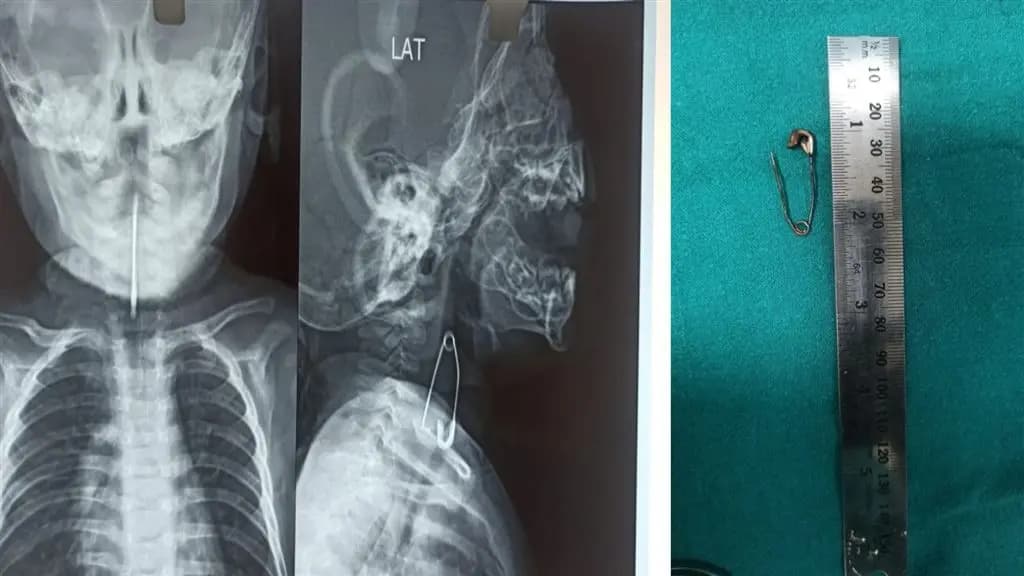

Calcutta Medical College: পাঁচ মাসের শিশুর শ্বাসনালীর কাছে আটকে ছিল মুখ খোলা সেফটিপিন, নিয়ে আসা হল কলকাতা মেডিক্যাল কলেজে, তারপর?